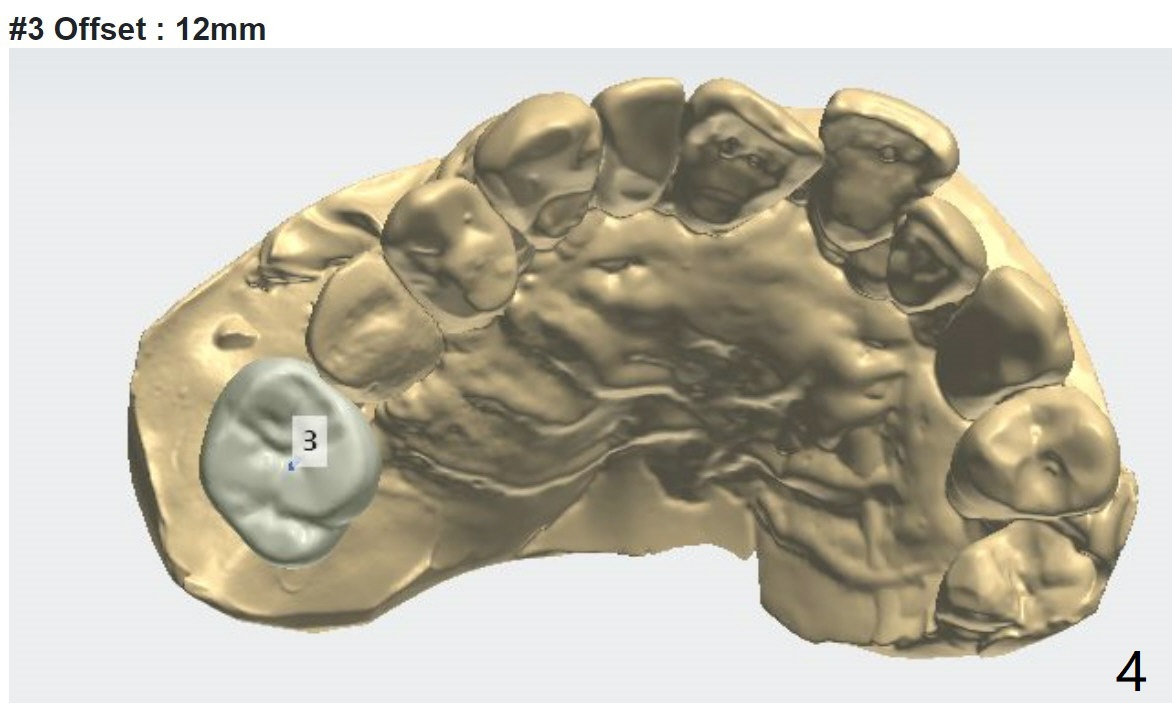

2nd Placement

Post implant removal and bone graft, the sinus floor must be soft and easily penetrated. Use Magic Sinus Lifter and sticky bone.